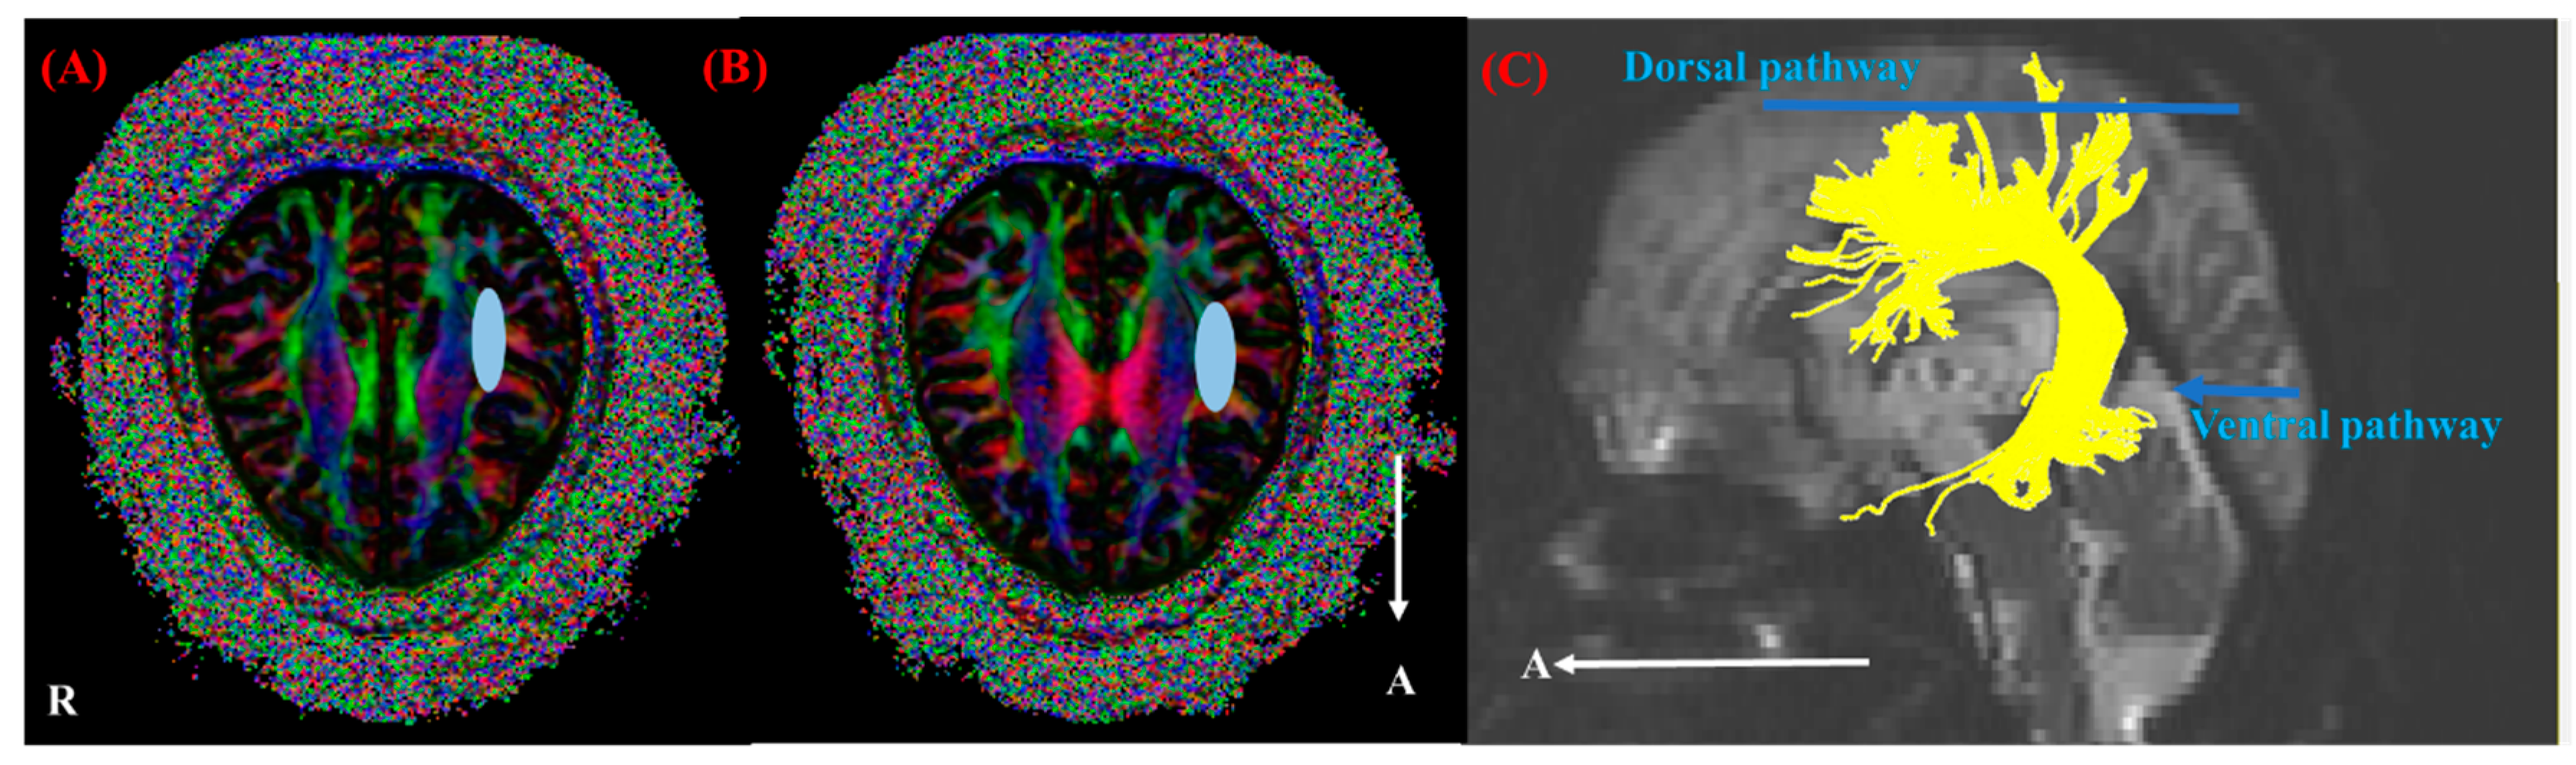

2.4. Fiber Tracking